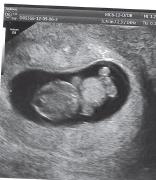

a to mój Ptasiek - nie wiem czy mi się uda wrzucićZobacz załącznik 497474

![]()

pscółka i spółka- cudowna foteczka

pscółka, ale faaaaajny :-)

pscółka - widocznie tak miało być a Ptasiek super